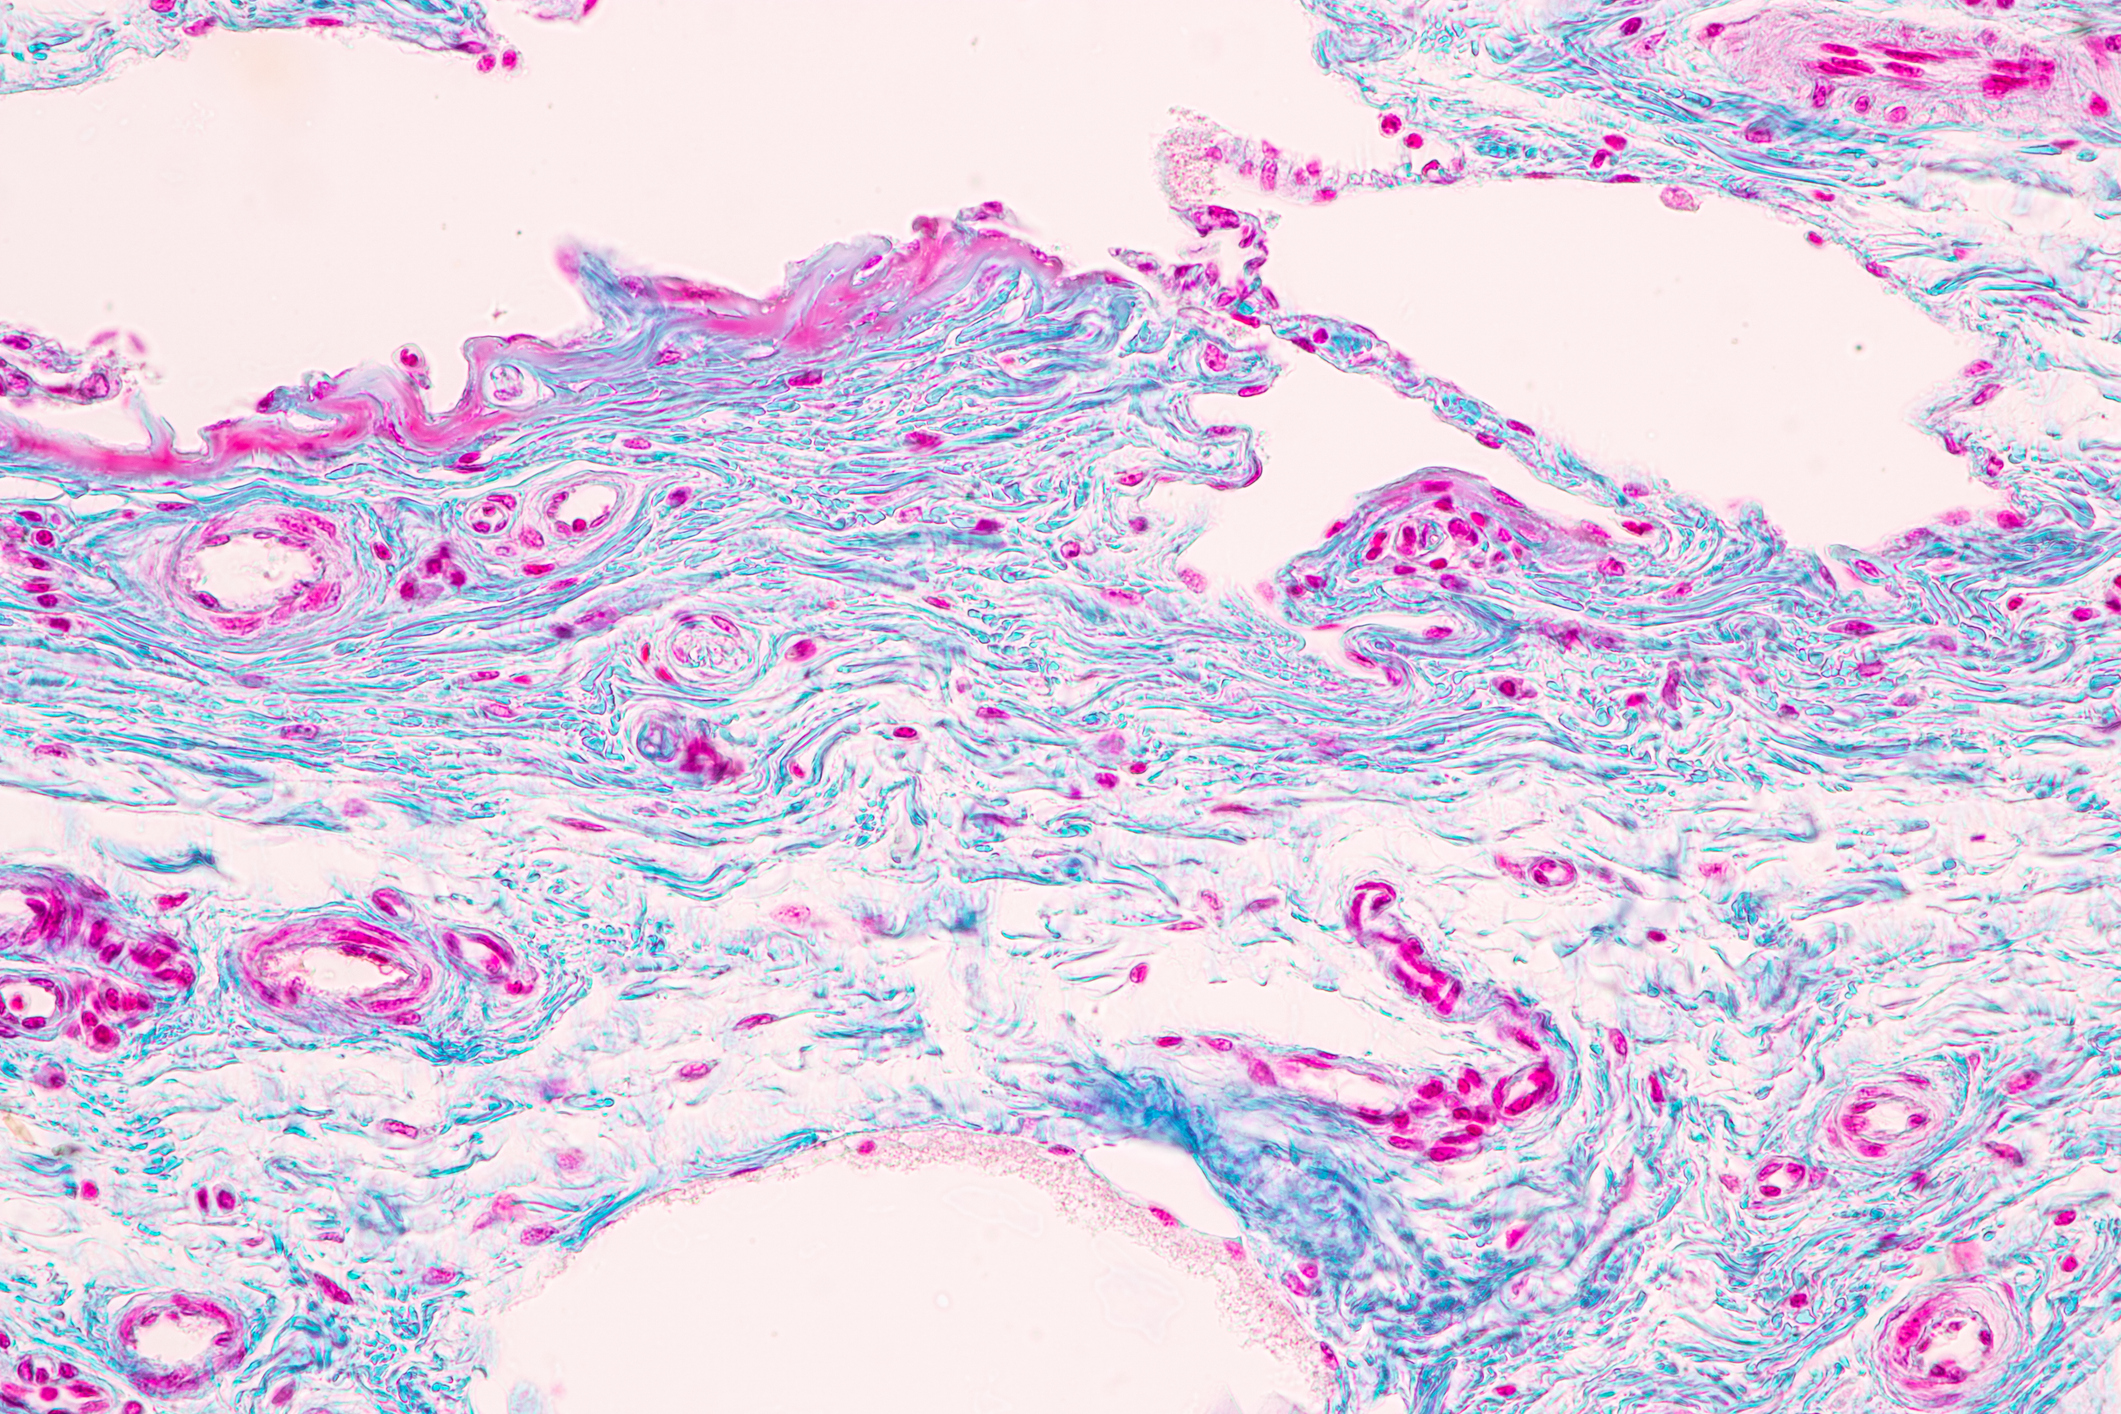

The two main primary vaginal cancers are named after the cells from which they develop: